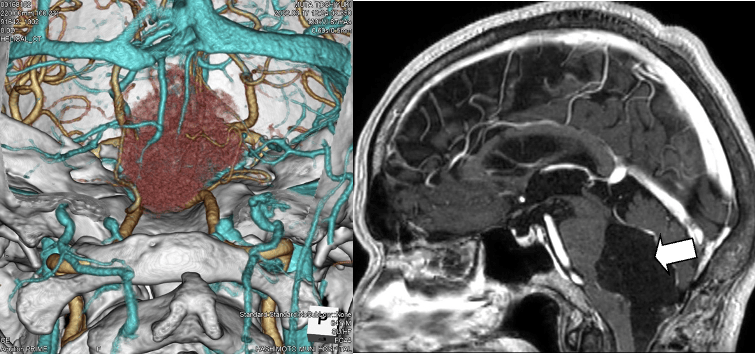

脳腫瘍(ナビゲーション手術、術中神経モニタリング併用)

当科では「画像支援ナビゲーション手術」を行っています。この手術で使用されるMedtronic社製のニューロナビゲーターStealth Station 8は、光学式のみならず磁場式トラッキングシステムを搭載しており、自動車の道案内に用いられる‘カーナビ’のように病変部と周辺組織の立体的位置を正確に表示してくれます。そのため、手術の際にどこを切開しどのように進めば安全に病変部まで到達できるのか、といったことが一目瞭然です。その結果、神経や血管を傷つけることなく安全に病変部を取り除くことができるようになり脳腫瘍の治療で成果をあげています。さらに、重要脳神経や重要機能を司る脳(手足の動き、言語)近傍脳腫瘍摘出時には神経モニタリングを併用し、画像支援ナビゲーションと共に病変部を切除する精度を高めるだけでなく安全性の向上にも役立っています。

脳幹周囲の脳腫瘍も、比較的安全に摘出可能